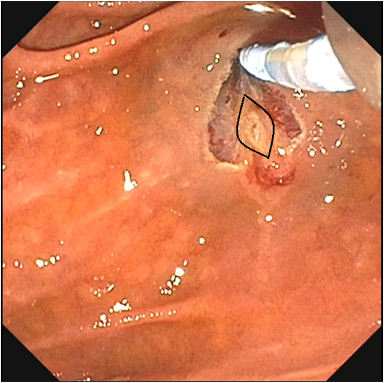

Endoscopic image outlining the ampullary os (black lines). Note its distinct appearance (does not stain with methylene blue) when compared with adjacent submucosal tissue (stains with methylene blue).

Prior to initiation of the incision, a targeted submucosal injection of dyed lifting solution was placed just above the ampullary orifice. This created a controlled submucosal cushion and enhanced visual differentiation among mucosa, submucosa, and deeper layers during dissection. Layer-by-layer needle-knife sphincterotomy was then performed, resulting in successful identification and cannulation of the bile duct without adverse events.